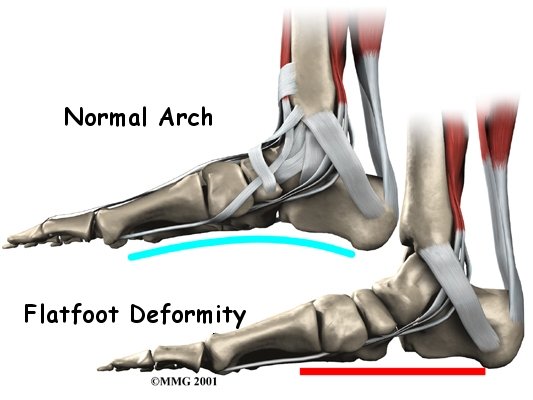

Multiple factors can contribute to posterior tibial tendon problems. Patients with flat feet are at a higher risk of having a posterior tibial tendon problem because of the persistent stretch on the tendon. Having flat feet can contribute to posterior tibial tendon problems, but conversely, posterior tibial tendon problems can lead to the medial arch of the foot dropping causing a flat foot.

The symptoms of tendonitis of the posterior tibial tendon include pain in the instep area of the foot and swelling along the course of the tendon. In some cases the tendon may rupture due to the degeneration of the tendon. Rupture of the tendon leads to a fairly pronounced flat foot deformity that is easily recognizable. In addition, a patient with a ruptured tendon is unable to rise up very high onto their toes, which also leads to the suspicion of a ruptured tendon.

Fusion

Finally, in cases which have been neglected and a fixed flatfoot deformity is present, a fusion (or arthrodesis) of the foot may be required. A fusion is an operation where a joint between two bones is removed and the two bones on either side of the joint are allowed to grow together, or fuse. This type of operation is used to stop pain from joints that are worn out. It can be used to realign the bones when the mechanisms for maintaining normal alignment are lost, such as when the tendons and ligaments no longer work properly. Usually, several joints must be fused to control a flatfoot deformity that develops after a posterior tibial tendon rupture.